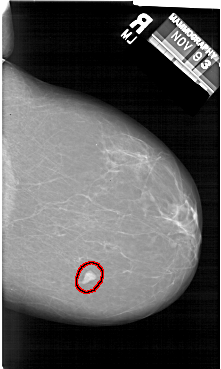

FILE: A_1412_1.RIGHT_CC.OVERLAY

TOTAL_ABNORMALITIES 1

ABNORMALITY 1

LESION_TYPE MASS SHAPE IRREGULAR MARGINS CIRCUMSCRIBED

ASSESSMENT 4

SUBTLETY 5

PATHOLOGY BENIGN

TOTAL_OUTLINES 1

BOUNDARY

RIGHT_CC LINES 6631 PIXELS_PER_LINE 3961 BITS_PER_PIXEL 12 RESOLUTION 43.5 OVERLAY